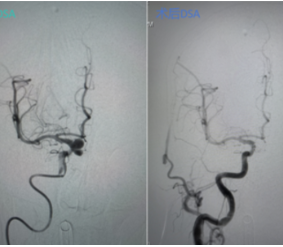

术后即刻造影显示,动脉瘤腔内血流消失,载瘤动脉通畅无阻,手术取得圆满成功,患者已康复出院。